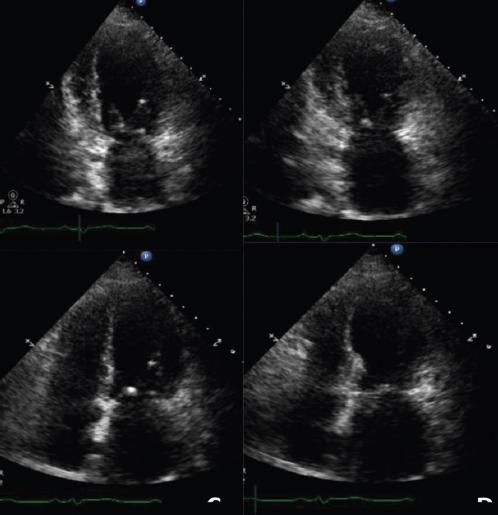

Transthoracic echocardiography (Figs. 2 and 3) showed akinesia in the middle and apical third of all walls with a LV ejection fraction (LVEF) of 30%, pulmonary systolic arterial pressure (PSAP) 45 mmHg and a normally functioning prosthetic aortic valve with a small paravalvular leak. It is important to highlight that the patient had an echocardiogram of November 2017, with normal contractility and LVEF of 70%.

Figure 2 Echocardiogram in 4-chambers view and 2-chambers view at systole and diastole showing the apical akinesia, and left ventricular ejection fraction 30%, with classical apical ballooning, during the cardiomyopathy.